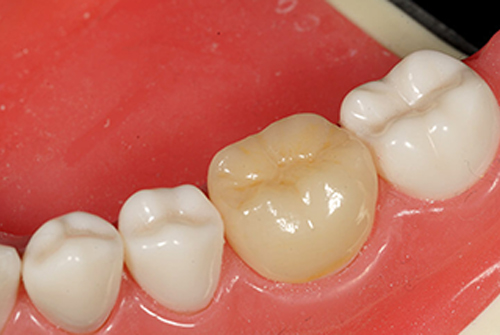

ジルコニア:

非常に硬い材質ですのでそれ自体が壊れたりすることはないですので、セメントの寿命が関係してきます。単色のためお色見合わせはあまりできませんが、最新のジルコニア(FCZ)であればお色見合わせが可能で、硬さもよりはに近いものとなっております。